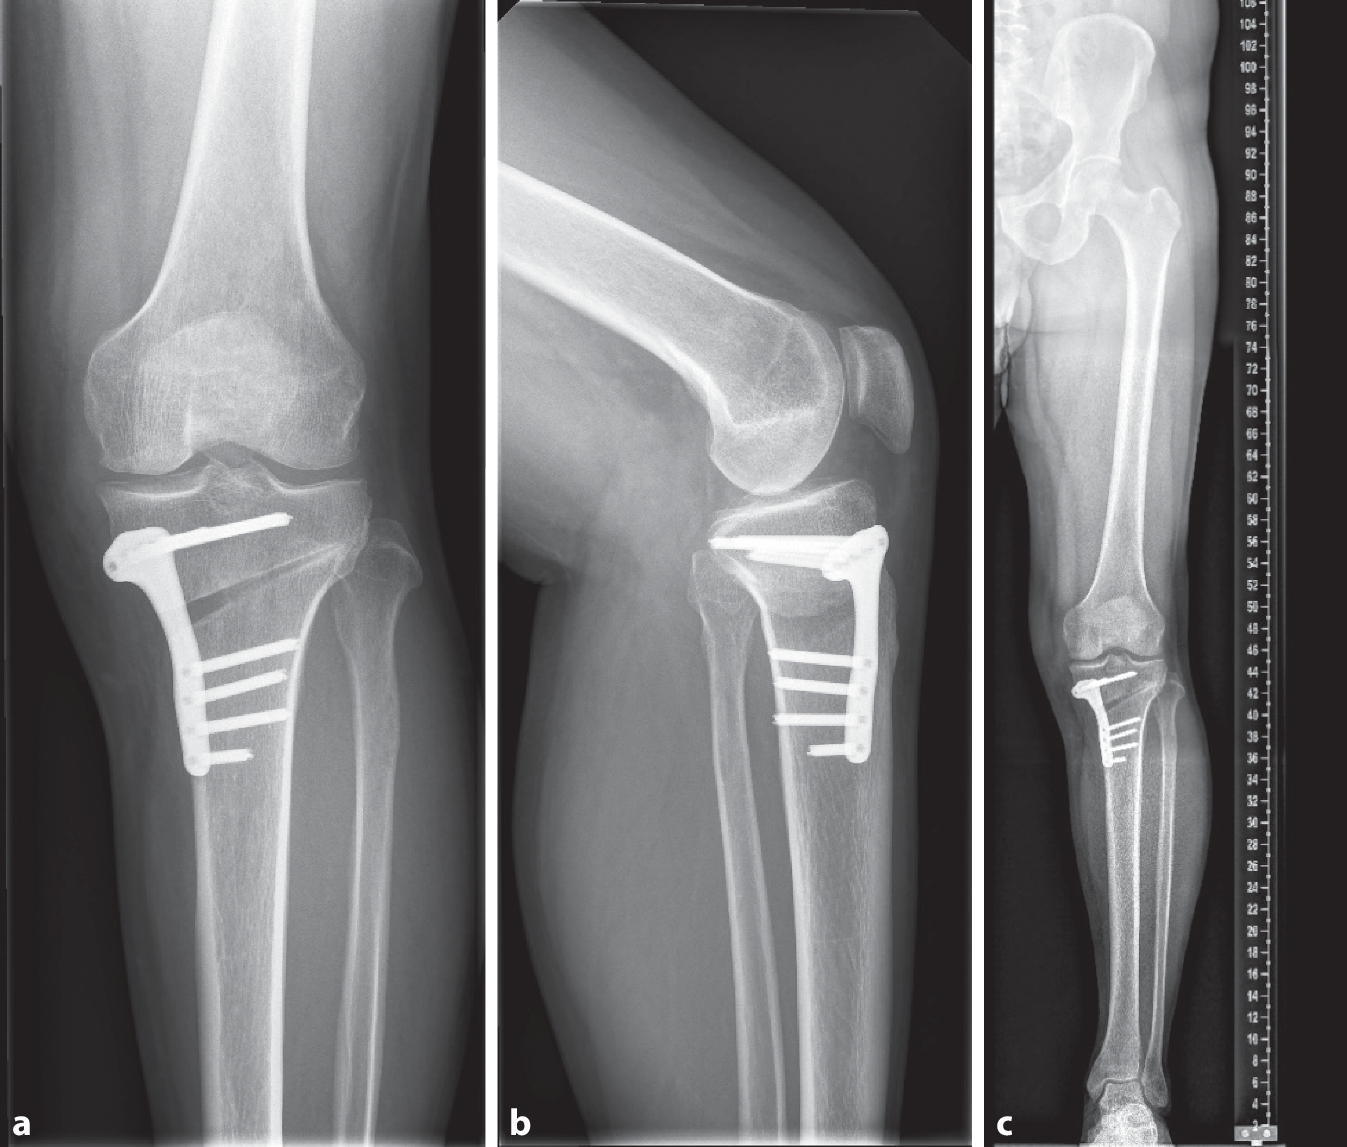

Neben einer Behandlung der radiären Verletzung des medialen Meniskus mittels Rebar-Nahttechnik (Abb. 3), wurde zusätzlich eine medial öffnende HTO zur Korrektur der varischen Beinachse und zur Entlastung des medialen Kompartiments geplant (Abb. 2b). Nach der operativen Versorgung, erfolgte die Röntgenkontrolle im anteroposterioren (Abb. 4a) und seitlichen Strahlengang (Abb. 4b). Zusätzlich wurden Beinganzaufnahmen zur Kontrolle der Winkelverhältnisse angefertigt (Abb. 4c). Da die Ergebnisse mit der Planung übereinstimmten, wurde dem Patienten eine komplette Entlastung für sechs Wochen, mit anschließender schrittweiser Erhöhung der Belastung bis hin zur Vollbelastung in den Wochen sechs bis acht, empfohlen. Während der ersten zwei Wochen soll das Bein mittels Knieorthese in Streckstellung und danach für vier Wochen auf 0/0/90° limitiert werden. Zwölf Wochen nach der Operation wurde eine Folgeuntersuchung durchgeführt, die ein nahezu beschwerdefreies Patientenbild zeigte.

Abb. 4

Darstellung der postoperativen Ergebnisse. a Postoperatives Röntgenbild des Kniegelenks im anteroposterioren Strahlengang. b Postoperatives Röntgenbild des Kniegelenks im seitlichen Strahlengang. c Postoperative Beinganzaufnahme

Die HTO diente im präsentierten Fall der Korrektur der varischen Beinachse von 9° auf 2,4°. Auch der MAD konnte dadurch von 32 auf 8 mm gesenkt und der FSA-mTA von −1,1° auf 5,5° erhöht werden. Wie oben genannt, zielte dieses Prozedere auf eine adäquate Kraftverteilung und eine Stressabnahme des geschädigten medialen Meniskus ab. Dadurch soll einerseits das Risiko für ein Versagen der Meniskusnaht reduziert und andererseits eine Verbesserung der Symptomatik erreicht werden.